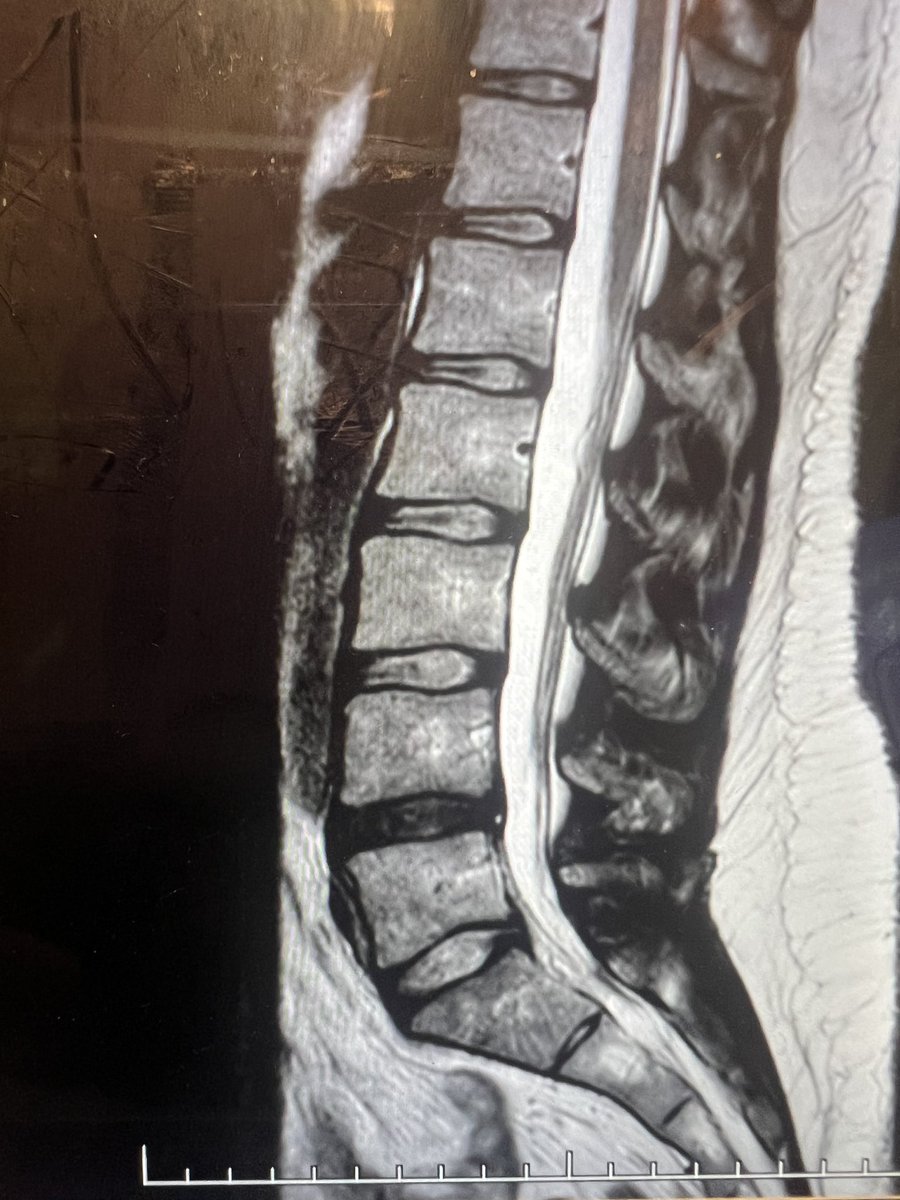

Bibrachial amyotrophy, superficial siderosis, and spinal cord herniation are three long-term sequelae of a ventral spinal CSF leak. This is the first patient we’ve ever seen who had all three. The cord herniation slowed down the leak Spinal CSF Leak Foundation SSRA | Living with SS